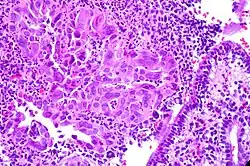

Die Zervizitis, Cervicitis (von Cervix für Gebärmutterhals) oder Gebärmutterhalsentzündung ist eine Entzündung des Gebärmutterhalses.[1][2]

Die Diagnose ergibt sich aus Kolposkopie mit Abstrich, der Infektionserreger kann mittels PCR oder HPV-DNA-Tests bestimmt werden.[1]